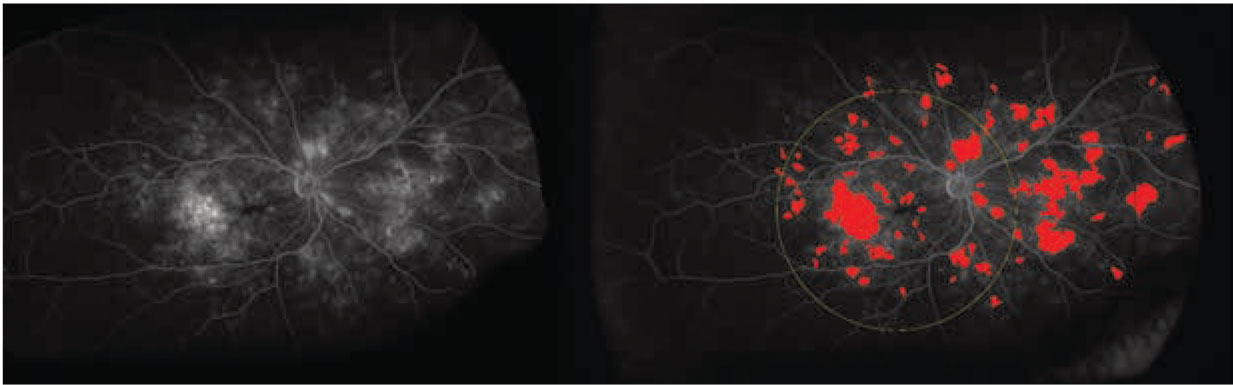

The labor-intensive nature of manual feature assessment had been a barrier to more widespread use. Recently, methods and systems have been developed to provide in-depth evaluation of leakage features, microaneurysm counts, ischemic burden and vascular characteristics (Figure 4).15,16

Automated angiographic quantitative assessment of UWFA features in DR has been shown to be strongly linked to DR severity.20 The quantitative assessment of these disease burden features may be critical in optimizing predictive assessment for risk of progression or DR-related complications. Panretinal leakage index, panretinal ischemic index and total microaneurysm counts are all strongly correlated with DR severity.20

The panretinal leakage index, in particular, has been associated with predicting additional DR-related complications, such as vitreous hemorrhage and DME.21,22 These quantitative parameters also provide a unique opportunity for evaluating a longitudinal treatment response. Using an automated UWFA system, intravitreal anti-VEGF therapy has demonstrated dramatic improvements in leakage index and total microaneurysm counts in DR.21,23 In fact, one recent trial used the panretinal leakage index as the key biomarker for therapeutic decision-making and demonstrated similar efficacy results to DR severity-based treatment decision-making.24 Leakage node distribution and morphology have also been linked to treatment interval tolerance in DME.25

Figure 4. Examples of quantitative leakage measurements on fluorescein angiography in diabetic retinopathy: (left) the original ultra-widefield FA scan; and (right) UWFA scan showing automated segmentation of leakage activity. |